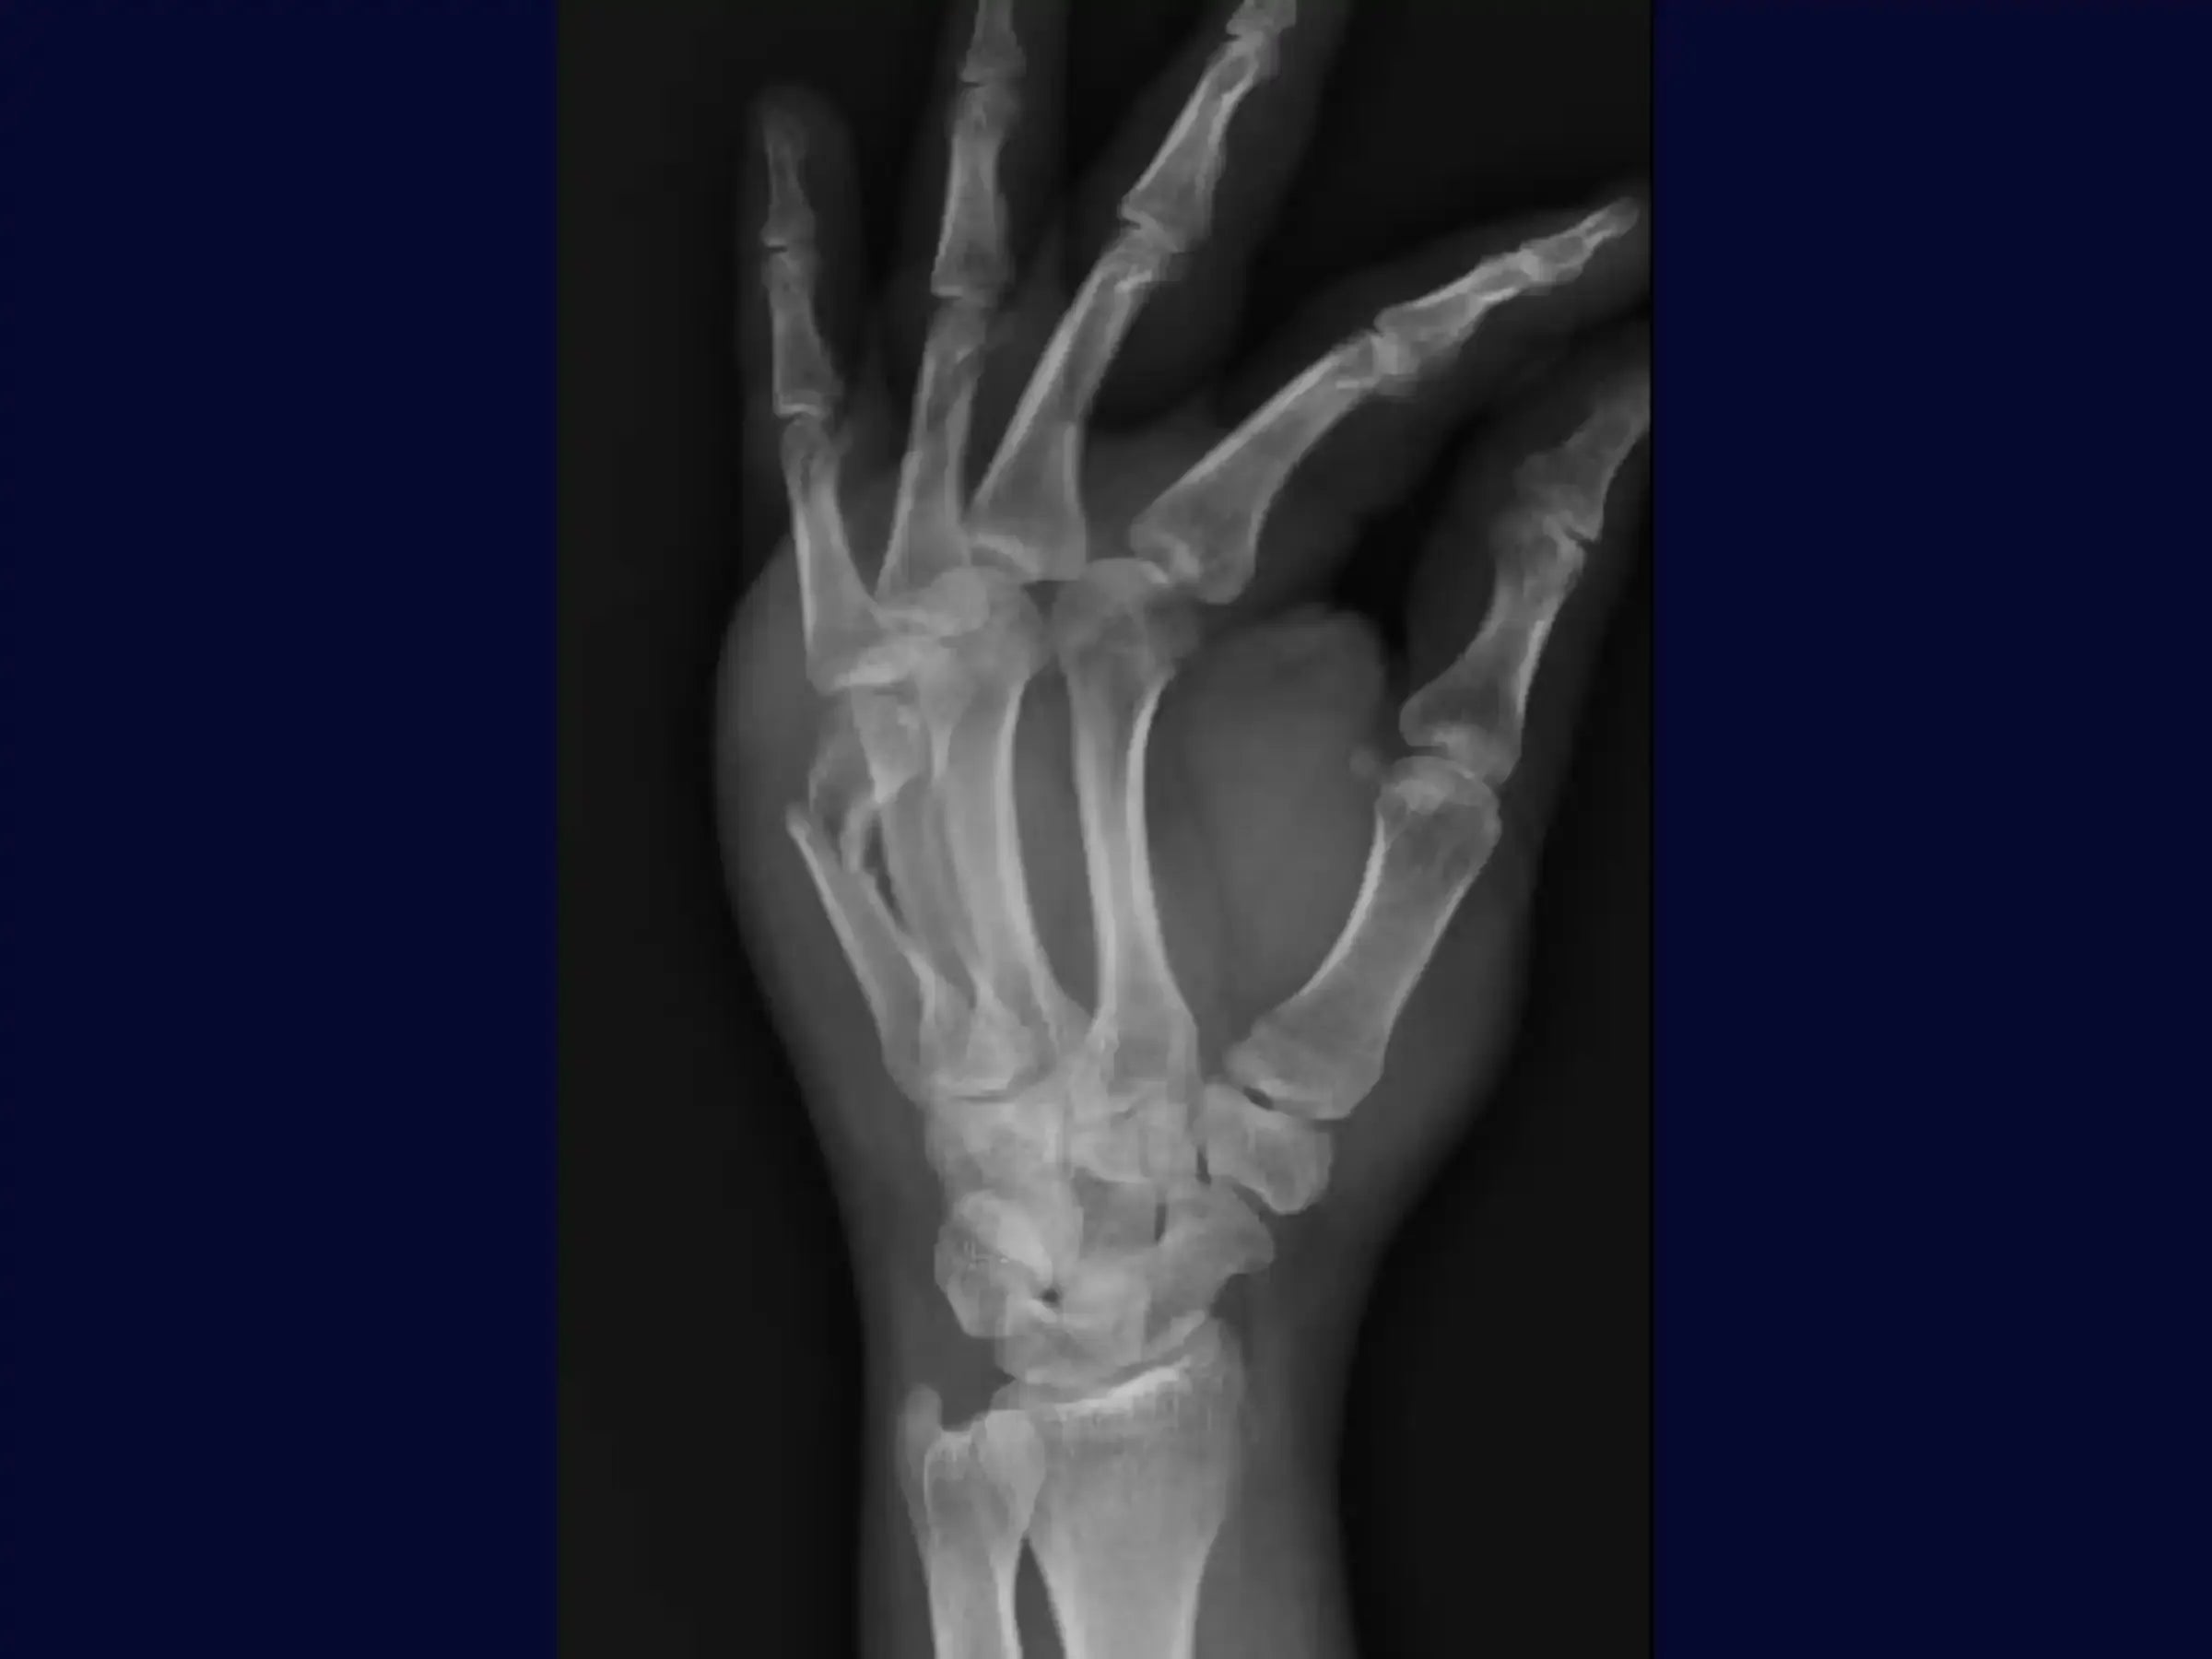

Fractura del cuello del quinto metacarpiano (fractura del boxeador)

Domine el tratamiento quirúrgico de la fractura del cuello del quinto metacarpiano, conocida como "fractura del boxeador", especialmente cuando la angulación supera los 40 grados. Esta formación proporciona una introducción técnica a la reducción y fijación con tornillos de doble compresión, utilizando un enfoque mínimamente invasivo para optimizar la recuperación del paciente.

- Planificación preoperatoria basada en radiografías.

- Evaluación radiográfica y planificación precisa: Aprenda a interpretar radiografías para identificar indicaciones quirúrgicas. Domine las marcas preoperatorias con un bolígrafo dermográfico, alineándolas con la diáfisis del quinto metacarpiano en las proyecciones anteroposterior (AP) y lateral para guiar la guía.